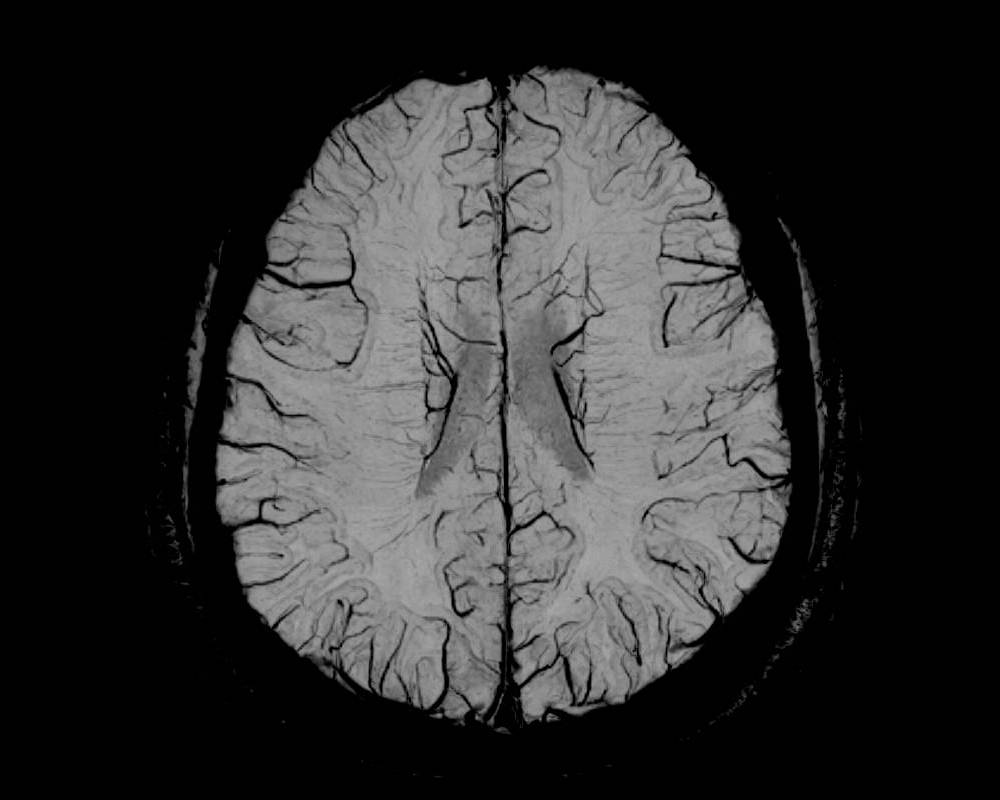

Клиникалық суреттер